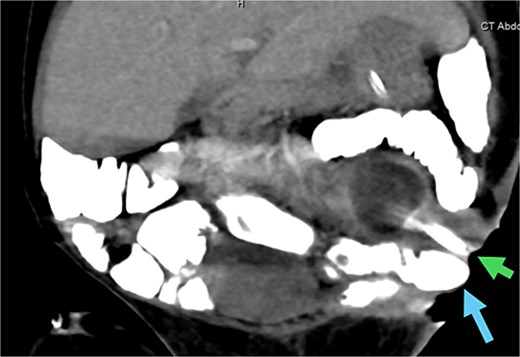

Development of new enterocutaneous fistulas after failed jejunostomy closure. Green arrow: ECF number 1. Blue arrow: ECF number 2. Yellow arrow: the new burst wound anastomosis site.

An abdominal CT scan with oral contrast revealed two ECFs: the first connected to the small bowel (Fig. 6, green arrow, corresponding to fistula number 1 in Fig. 5), and the second connected to the proximal sigmoid colon (Fig. 6, blue arrow, corresponding to fistula number 2 in Fig. 5). Furthermore, an enteroenteric fistula between the ileum and rectosigmoidal junction was noted (Fig. 7, red arrow).

CT abdomen with oral contrast showing two enterocutaneous fistulas. Green arrow: fistula connected to the small bowel. Blue arrow: fistula connected to the proximal sigmoid colon.